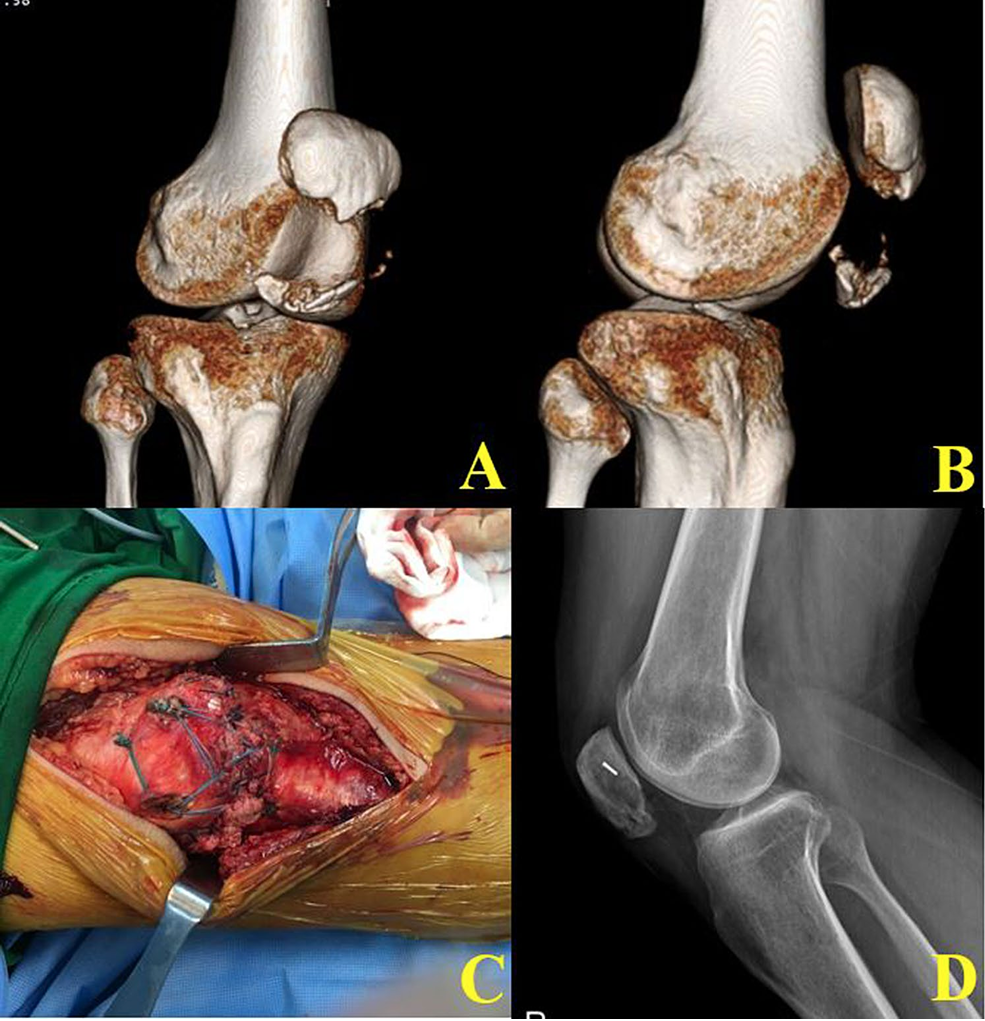

图2 翻开粉碎的下极骨折块后,将两个带两股超强编织缝线的5.5-mm金属锚钉(TwinFix Ti; Smith & Nephew Endoscopy, Andover, MA, USA)置入骨折髌骨的主要近端骨块。在近端大骨块上为Footprint锚钉钻孔,位置从近端髌骨缘上缘以远2 cm开始,骨表面垂直。

在本研究采用的技术中,患者取仰卧位,使用止血带。于髌骨至胫骨结节作正中直切口,暴露骨折部位(图2a)。翻开粉碎的下极骨折块后,对上极骨折床进行清创和刮除。

将两个带两股超强编织缝线的5.5-mm可吸收或金属锚钉(Twin-Fix Ti;Smith & Nephew Endoscopy, Andover, MA, USA)置入骨折髌骨的主要近端骨块(图2b)。若患者为骨质疏松的老年患者,我们更倾向于使用高抓持力的金属锚钉而非可吸收锚钉。两个锚钉之间的宽度尽可能达到1 cm,并靠近髌骨关节面(图2c)。若远端骨块有足够空间钻孔,建议钻孔。通过这些远端骨块上的孔,我们穿入缝线锚钉的线。然而,如果远端骨折块非常粉碎,则在髌腱上行褥式缝合打结。使用Mayo针将超强编织线穿过髌腱或钻孔后的下方小骨折块。然后,将一个双线锚钉的所有四股线均通过髌腱或下方小骨块引出(图2d)。在C臂机引导下,拍摄前后位和侧位片以确保复位对线。此阶段使用C臂机确认锚钉方向是否过浅或过深。同时,应在矢状面上确认下方骨折块无倾斜。出于对固定强度不足的担忧,有2例病例加用了克氏针张力带钢丝固定。

从髌腱褥式缝合引出的每根缝线末端,穿过4.5 mm无结锚钉(Footprint anchor; Smith & Nephew Endoscopy, Andover, MA)末端的孔。在近端骨折块上为Footprint锚钉钻孔,位置从近端髌骨缘上缘以远2 cm开始,骨表面垂直(图2e)。此时,在近端髌骨的坚硬皮质骨表面预先用3.2 mm钻头钻孔。在持续张力下,将两个Footprint锚钉插入预先钻好的孔中,并检查这些粉碎性骨折的稳定性(图2-F)。若无法获得坚强的骨折固定,我们则额外加用克氏针张力带钢丝固定,并且在髌骨骨折达到骨愈合前,我们非常谨慎地进行监督下的物理治疗。最后,逐层缝合伤口。

术后即刻鼓励进行股四头肌等长收缩练习。膝关节支具在完全伸直位佩戴四周,术后4周开始进行关节活动度和股四头肌锻炼。末次随访X线片确认这些粉碎性下极骨折完全愈合(图3)。

图3 严重粉碎性髌骨下极骨折的术前及术后2年随访X线片